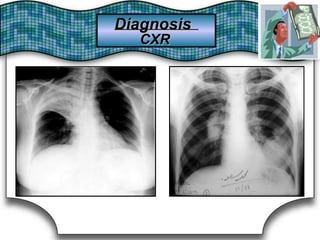

Chest X Ray (CXR)X Ray (CXR)Chest

Chest RadiographRadiographChest Suggestive DiagnosisSuggestive Diagnosis

Cardiomegaly, increasedincreasedCardiomegaly,

pulmonary vascular distributiondistributionpulmonary vascular

Chronic heartheart failure,failure, mitralmitral valve stenosisvalve stenosisChronic

Cavitary lesionsCavitary lesions Lung abscess, TB,TB, necrotizing carcinomanecrotizing carcinomaLung abscess,

Diffuse alveolar infiltratesinfiltratesDiffuse alveolar Chronic heartheart failure,failure, pulmonary edema,pulmonary edema, aspirationaspirationChronic

Hilar adenopathy oradenopathy or massmassHilar Carcinoma, metastaticmetastatic disease,disease, infectioninfectionCarcinoma,

HyperinflationHyperinflation COPDCOPD

Lobar oror segmentalsegmental infiltratesinfiltratesLobar Pneumonia, thromboembolism, obstructing carcinomathromboembolism, obstructing carcinomaPneumonia,

Mass lesion,lesion, nodules,nodules, granulomasgranulomasMass

Carcinoma,

granulomatosis,

metastatic disease, Wegener's

vasculitides

Carcinoma, metastatic disease, Wegener's

septic embolism,granulomatosis, septic embolism, vasculitides

Patchy alveolar infiltratesinfiltratesPatchy alveolar

Bleeding disorders, idiopathic pulmonaryBleeding disorders, idiopathic pulmonary

hemosiderosis, Goodpasture's syndromesyndromehemosiderosis, Goodpasture's